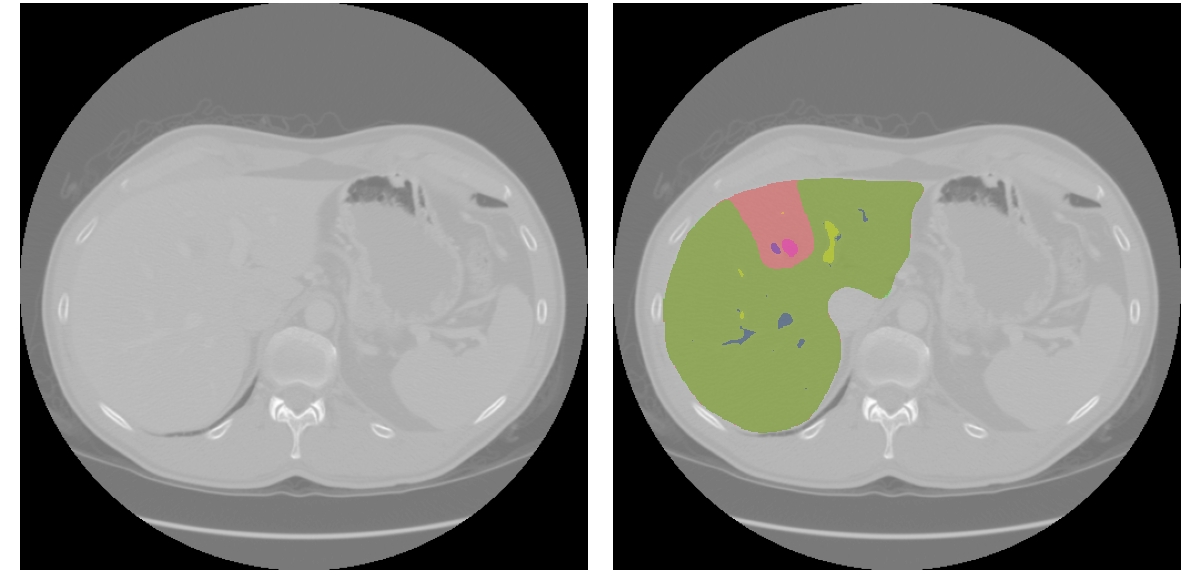

Refer to caption

Figure 2: Visualization of the dataset, including segmentation of the liver, residual liver, hepatic veins, portal veins, and tumors.

Datasets. We validate DyPro on the publicly available CRLM prognostic dataset from Memorial Sloan Kettering Cancer Center (MSKCC) [16] (Fig. 2). The cohort contains 197 patients with colorectal cancer liver metastases who underwent liver resection, with preoperative contrast-enhanced CT scans, radiologist-annotated segmentations of liver, residual liver, major vessels and metastatic lesions, and corresponding clinical variables (e.g., demographics, tumor burden, serum CEA, treatment regimen). Postoperative follow-up provides recurrence events and survival outcomes, enabling joint DFS and OS modeling.